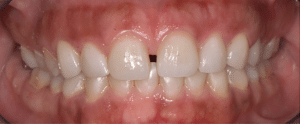

Mme AB vient en consultation pour deux raisons. La première est une douleur intense à chaque fois qu’elle boit ou mange froid. La deuxième est l’apparence de son sourire. Elle trouve que ses dents ont « raccourci » et qu’elles « s’effritent ». C’est devenu un complexe handicapant. À L’examen clinique on observe (Fig.1a, b, c, d, e) une usure vestibulaire de toutes les dents : plus prononcée au maxillaire et assez légère sur les incisives mandibulaires, une classe III canine et molaire droite, une classe I canine et molaire gauche avec une légère déviation des milieux et une usure importante des faces palatines du bloc IC maxillaire ainsi que des faces occlusales de 16 et 26. On constate aussi que les faces occlusales des autres dents sont moins touchées en apparence. On observe que les amalgames de 36 et 48 sont en relief par rapport à la dent support. Il est raisonnable de supposer qu’à l’origine ils devaient obturer une cavité et donc être à l’intérieur de la dent. Ceci témoigne donc aussi d’une forte usure sur 36 et 46. On observe enfin que les courbes de Spee sont complètement plates.

Fig.1a, b, c, d, e : Examen clinique.

Fig.1b.

Fig.1c.

Fig.1d.

Fig.1e.